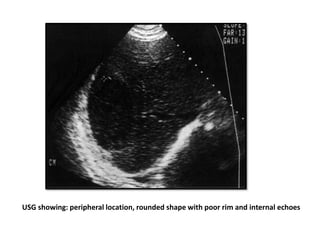

USG showing: peripheral location, rounded shape with poor rim and internal echoes

USG showing: peripherallocation, rounded shape with poor rim and internal echoes